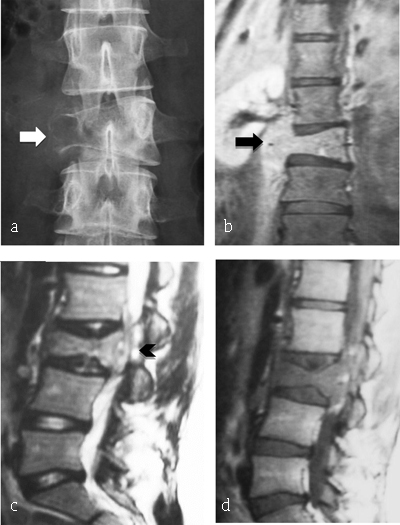

Figure 6

Ewing Sarcoma of L3. (a) Plain radiograph of lumbar spine reveals lytic lesion of right pedicle and right transverse process with partial vertebral collapse (arrow). (b, c, d) MR: coronal T2-WI, sagittal T2-WI and T1-WI after gadolinium reveal vertebral lesion of L3 with high signal intensity on T2-WI, enhancing after gadolinium injection and extending to prevertebral muscles (arrowhead) and to epidural space (arrow).